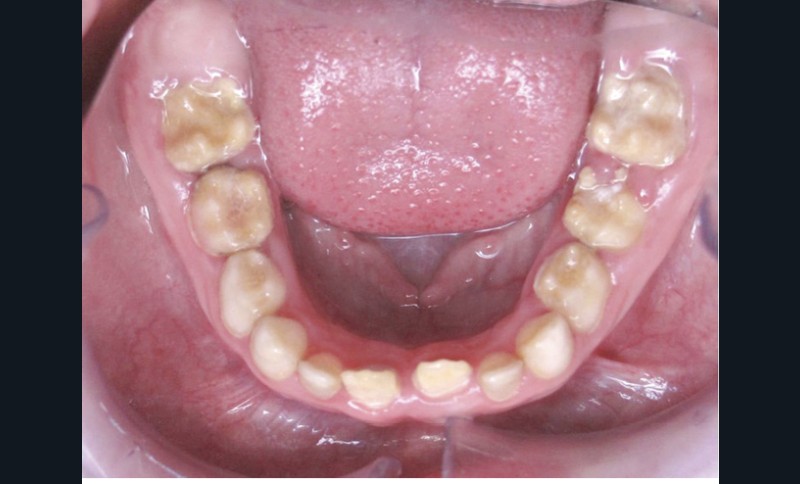

Il existe des anomalies dentaires (tabl. I) [1-12], mais aussi occlusales associées aux AI (fig. 1 et 2).

Selon de nombreuses études, l’anomalie occlusale la plus fréquemment retrouvée en association avec les AI est l’infraclusion antérieure, puisqu’elle est retrouvée chez 22 à 64 % des patients présentant cette affection, et encore plus chez les femmes [2,8,13-19]. Cette anomalie touche tous les types d’AI mais à des degrés très divers. Son incidence semble élevée dans les formes hypominéralisées, moindre dans les formes hypoplasiques et nettement moindre dans les formes hypomatures [8,17,18]. La sévérité de l’atteinte amélaire ne semble pas corrélée avec la présence ou l’intensité de cette malocclusion [17].